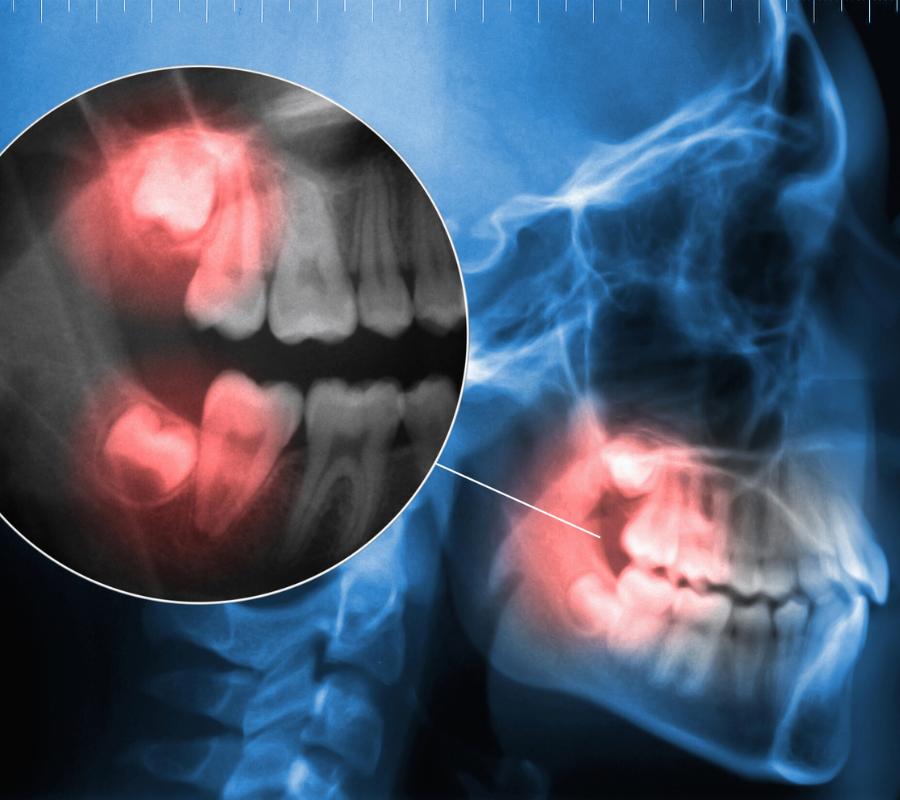

• State-of-the-Art Tools: Equipped with advanced diagnostic imaging and techniques, our clinic offers safe and accurate wisdom teeth removal for all patients.

• Address Painful Impactions: Impacted wisdom teeth can lead to infections and severe discomfort. Our expert team in Millcroft ensures effective treatment to eliminate these risks.